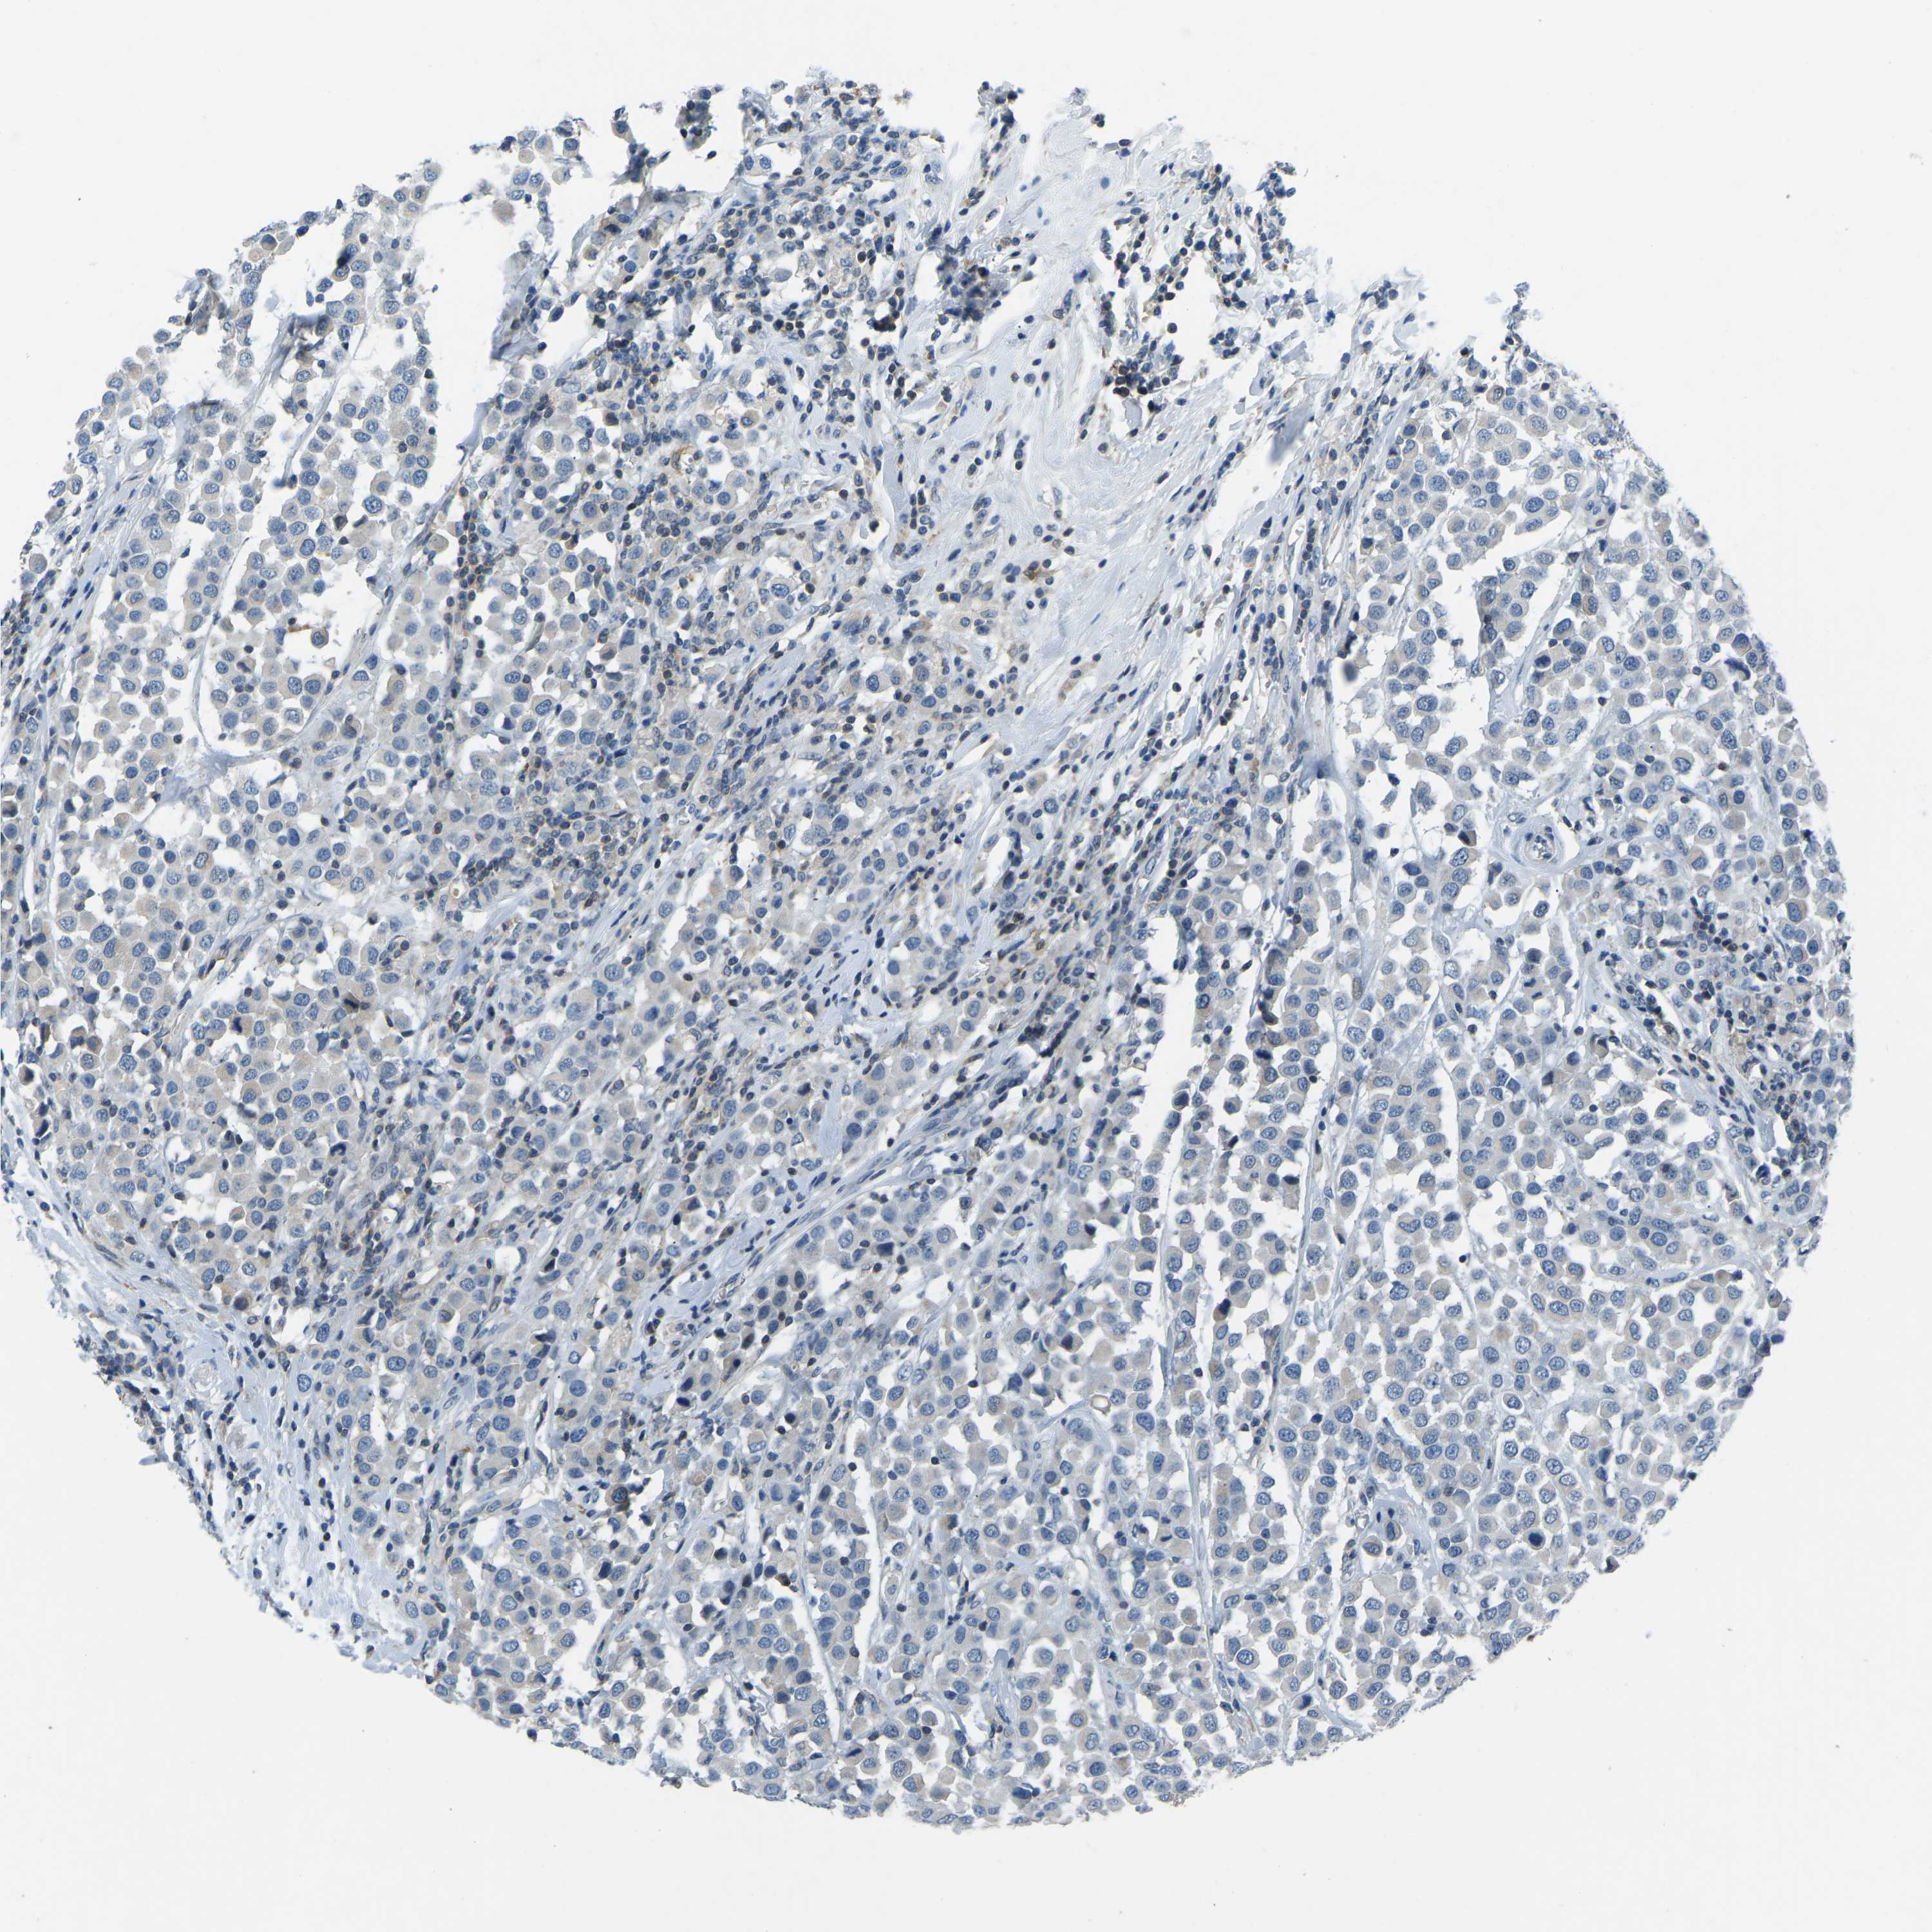

CANCER BREAST CANCER Show tissue menu

BRCA TCGA BRCA VALIDATION PROTEIN EXPRESSION

ANTIBODIES

AND

VALIDATION